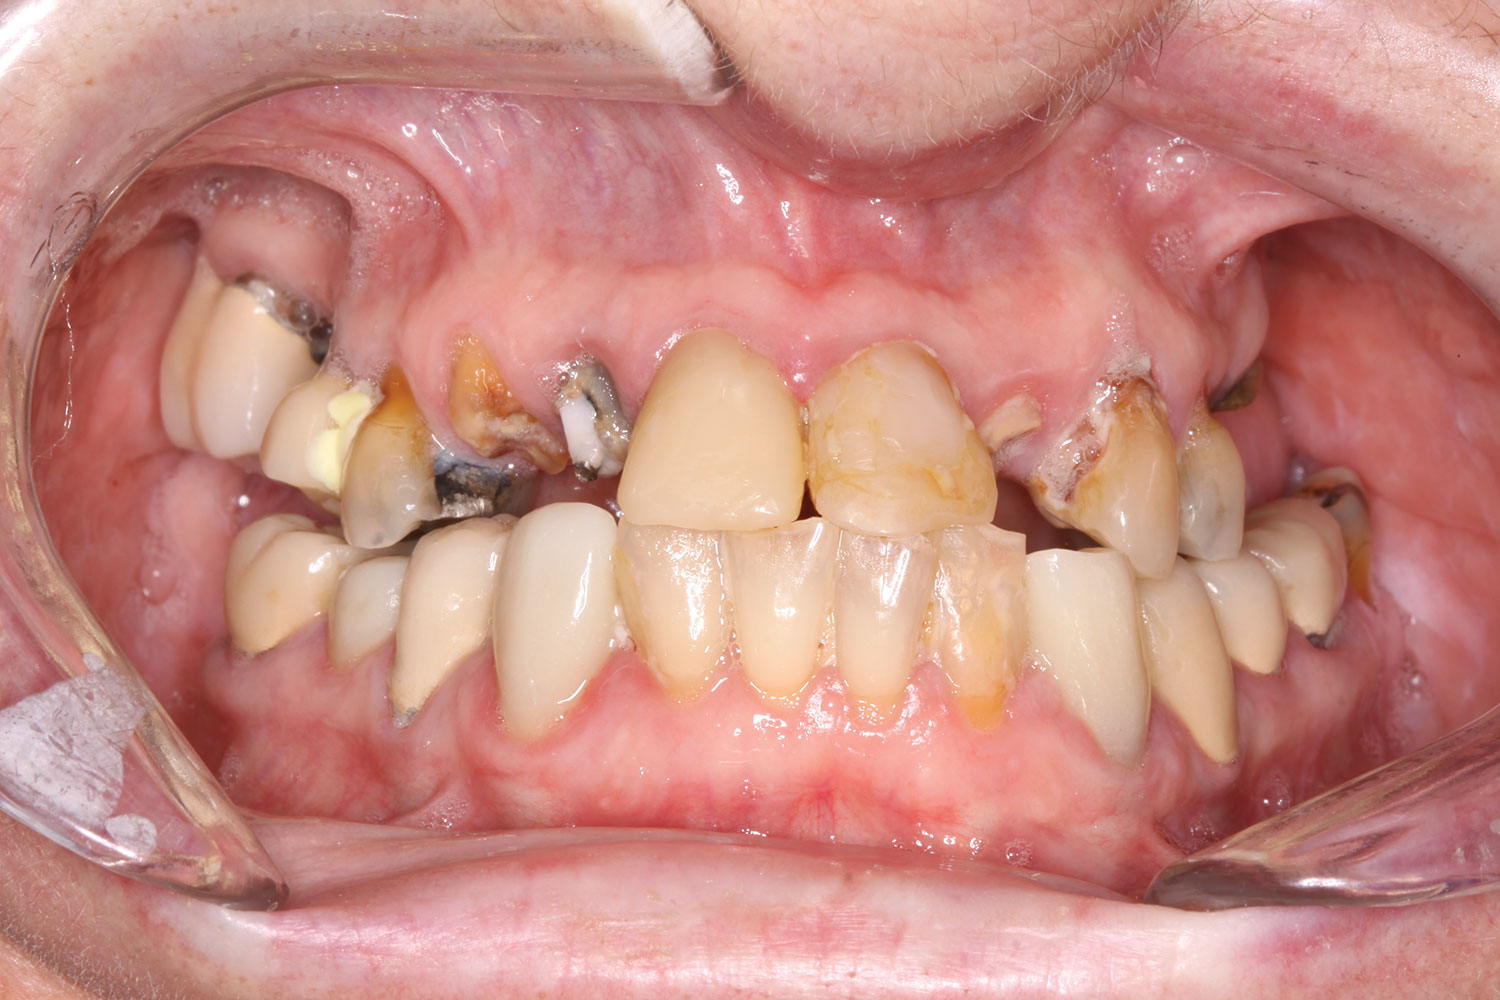

Fig 23. Case 3: Initial presentation for maxillary and mandibular immediate implant, immediate load provisional restorations. Full-face photograph.

Figure 23

Fig 24. Initial panoramic radiograph.

Figure 24

Fig 25. Initial clinical presentation, intraoral view.

Figure 25